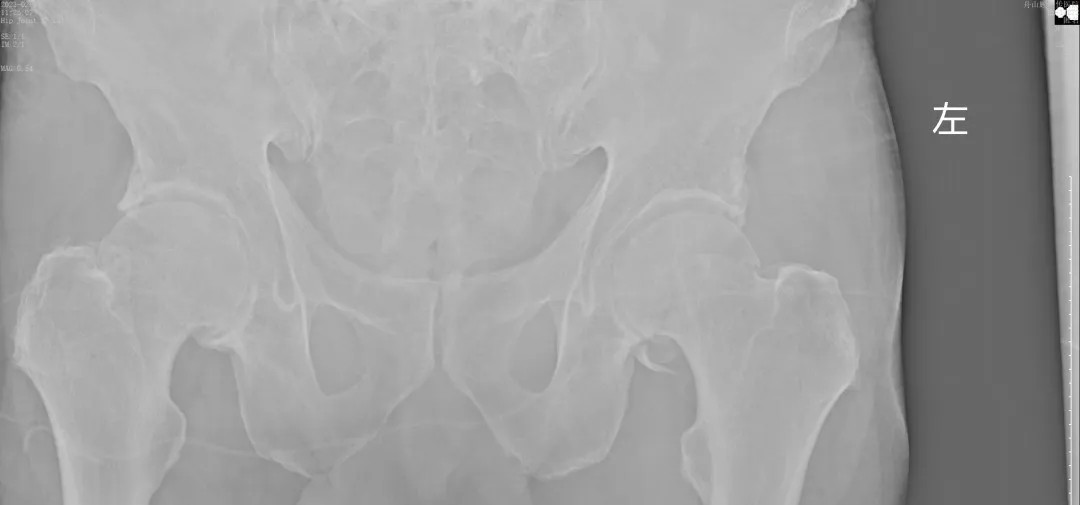

經(jīng)過(guò)王副主任認(rèn)真仔細(xì)的檢查,并結(jié)合X線攝片后,他告訴患者及其家屬:“周大爺是外傷導(dǎo)致的急性髖關(guān)節(jié)脫位、髖臼骨折!”一聽(tīng)脫位骨折了,患者及家屬焦慮萬(wàn)分,擔(dān)心手術(shù)給身體和經(jīng)濟(jì)帶來(lái)的巨大壓力。王副主任耐心告知周大爺一家人:“周大爺這種病情可以保守治療,用我們顧氏的正骨手法可以復(fù)位的,不需要開(kāi)刀,價(jià)格也實(shí)惠”。家屬聽(tīng)到不用做手術(shù),瞬間放心不少,表示非常愿意配合治療。

(術(shù)后復(fù)片  關(guān)節(jié)對(duì)位良好)